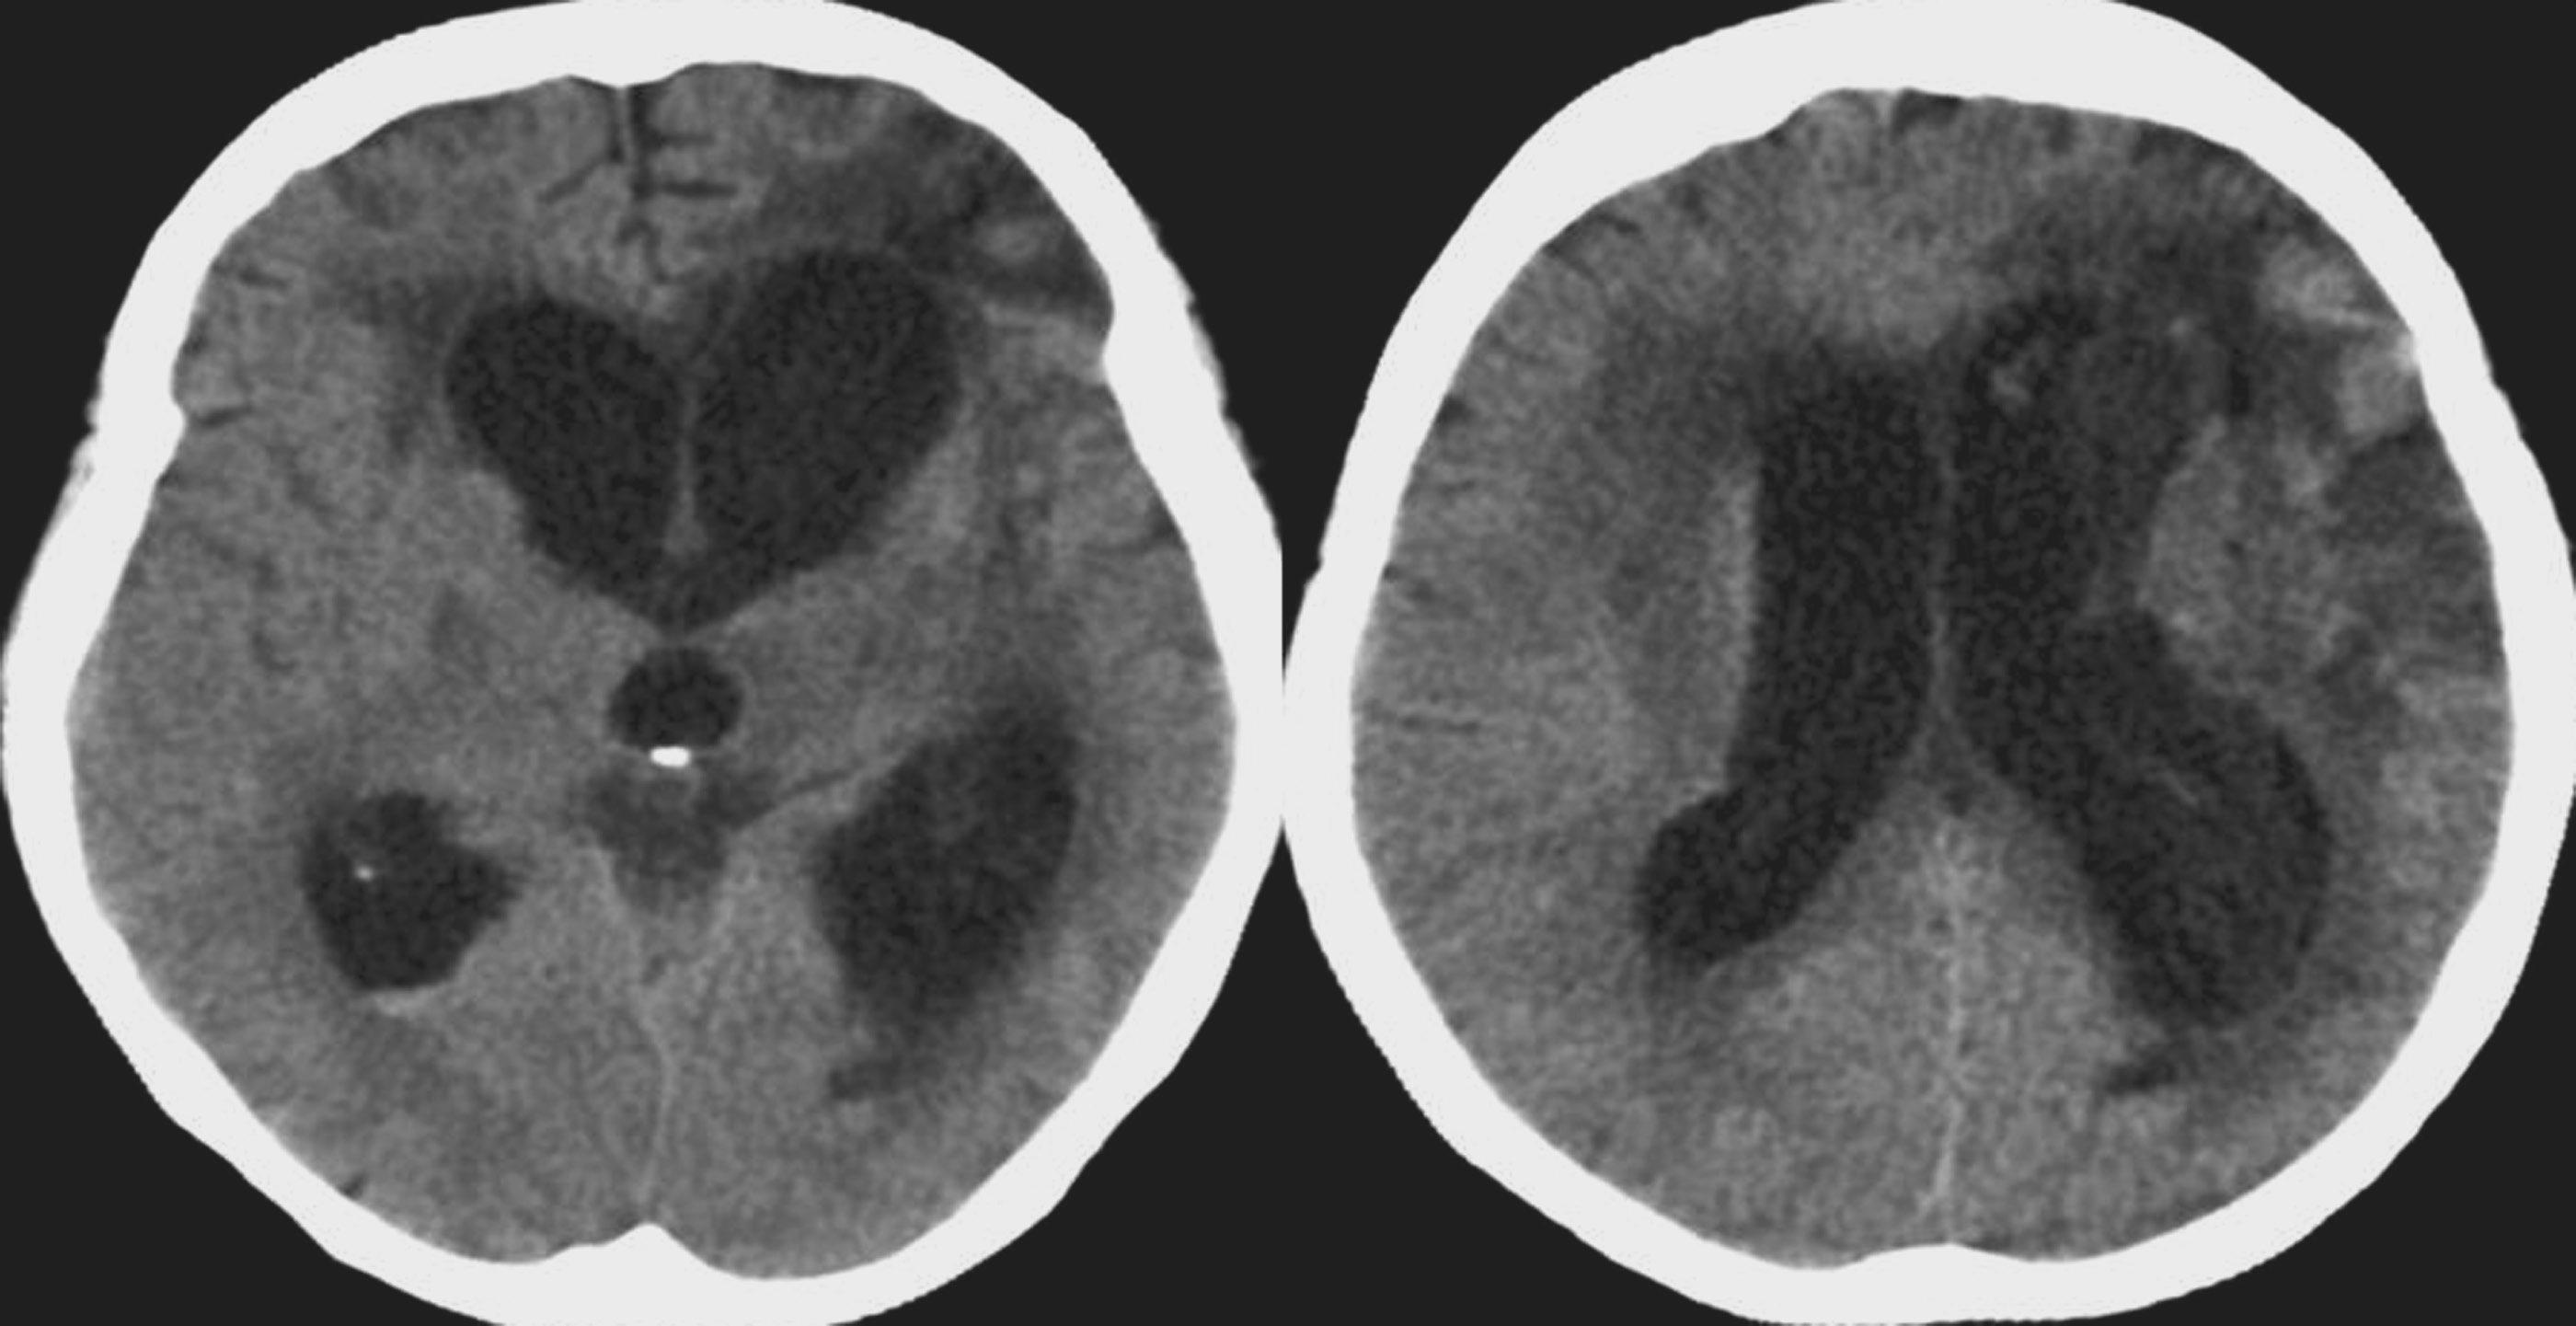

(1)CT表现(图5-1-1):

①脑室系统普遍扩大而蛛网膜下腔变浅或消失;②侧脑室额角和颞角变钝、变圆,枕角扩大出现较晚;③侧脑室周围白质内可见明显的低密度水肿带。

图5-1-1 高压力性脑积水的CT表现

辅助检查:头颅CT(图5-1-3)提示第三脑室见类圆形低密度病变,脑室普遍扩大,脑沟消失,伴侧脑室周围低密度水肿带。

图5-1-3 头颅CT表现

初步诊断:第三脑室内占位性病变;高压力性脑积水。